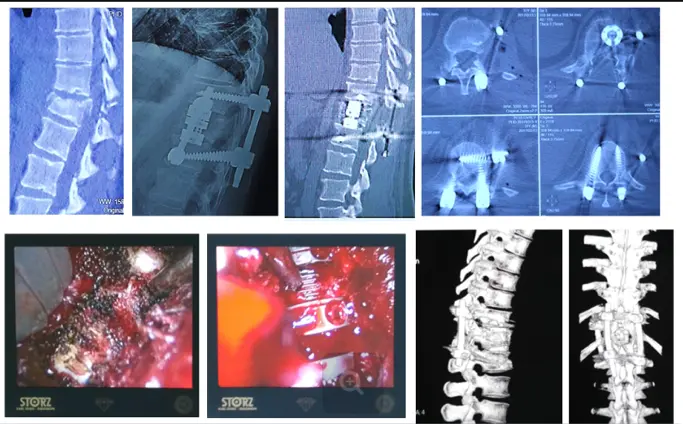

Видеоэндоскопический спондилодез телескопическим эндопротезом и чрескожная мини-инвазивная транспедикулярная стабилизация и при оскольчатом переломе второго поясничного позвонка.

Транспедикулярная мини-инвазивная стабилизация и бисегментарный межтеловой спондилодез с видеоэндоскопической ассистенцией при компрессионно-оскольчатом переломе первого поясничного позвонка.